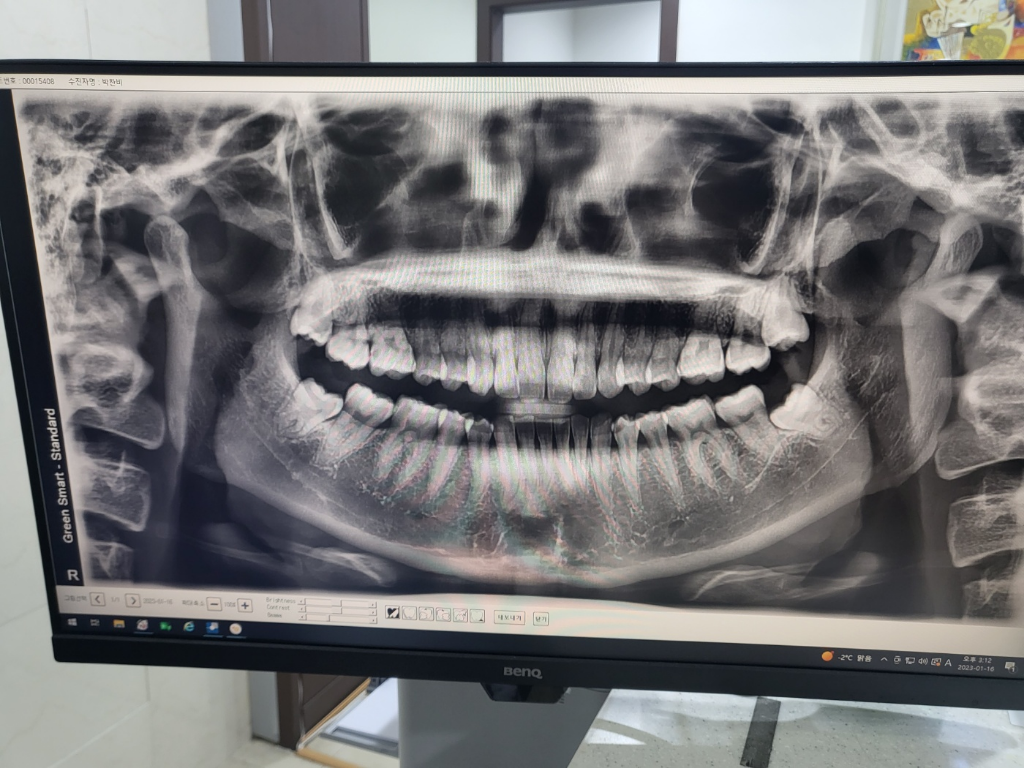

사랑니 모양 이정도면 뽑아야 할까요?

4개 다 있는데 왼쪽 아랫쪽 빼고 셋 다 나고 있습니다. 아픈 건 없는데 윗쪽 사랑니가 아랫쪽보다 먼저 나기 시작해서 밥 먹을때 아랫쪽 사랑니 자리 잇몸?이 씹혀서 아파요. 보니까 살짝 하얘졌는데 문제가 있을까요?

사랑니 나는 중인데 뽑아야 할까요? 아니면 다 나고서 뽑아도 될까요~~

사랑니 쪽 잇몸이 위쪽치아에 교합되면서 하얗게 보일수도 잇고 사랑니가 잇몸 바로 아래 잇어서 그럴수도 잇습니다. 불편하시면 4개다 발치를 하시면될것같습니다.

사진으로 봤을 경우에 아직 사랑니가 맹출되거나 하지는 않은 것으로 보입니다.

사랑니가 똑바로 나왔을 때는 그대로 사용할 수 있지만 사랑니가 기울어져 나거나 충치나 주변 조직의 염증을 유발하고 있다면 발치를 하는 것이 좋습니다 자세한 확인을 위해서 치과에서 진료를 받아 보세요

사랑니는 뽑으시는 것이 좋아보입니다. 다 나고 나서 뽑기보다는 충치가 생기기전에 빨리 뽑는것이 좋겠습니다.

사랑니는 다 맹출하고 나서 빼도 됩니다. 맹출방향이 이상하지 않고 옆 어금니를 누르면서 치근흡수를 할 정도로 영향을 주고 있지는 않습니다. 다만, 맹출중일 때는 잇몸이 부을 수 있고 잇몸과 사랑니, 옆 어금니 사이 틈으로 음식물이 잘 낄 수 있으므로 이 부위는 위생관리를 잘 해주셔야 합니다.